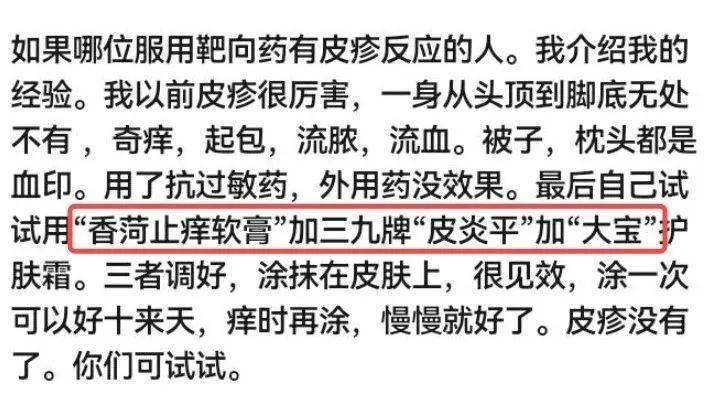

►关于皮疹

2022年11月19日在病友群收藏了一个皮疹应对的方法。我爸于2023年7月14-15日第三次复用白紫 卡铂 信迪利的治疗方案,2023年7月16日有轻度的皮疹反应,症状就是浑身痒,尤其膝关节和胳膊肘,用下面的方法抹了抹,效果很好。特地分享一下,我也算是借花献佛,有需要的觅友自行保存!

图片来源:患者提供

单免8次后有点进展,今年5月中旬我爸重启了化疗,因为最初白紫 卡铂效果很好,就复用了这个方案外加免疫药信迪利,总共用药四次,我爸还可以耐受,唯一不舒服就是皮肤痒,一挠就破,用了皮炎平 香荷止痒软膏 大宝效果也很好,不痒也就不用挠,试了单用皮炎平都不行。